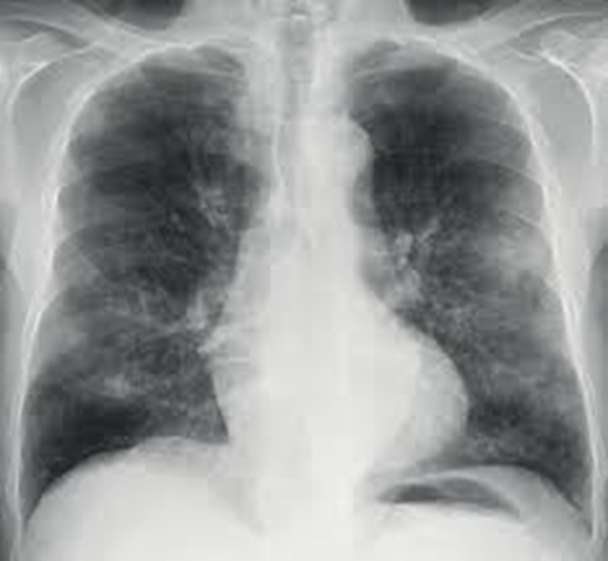

| Enfermedad leve | – Muchas veces es normal.- Opacidades en vidrio deslustrado periféricas de predominio inferior. |

| Enfermedad moderada | – Consolidaciones parcheadas periféricas de predominio inferior.- A veces, se observa la progresión hacia una mayor afectación de los campos medios y superiores. |

| Enfermedad grave | – Opacidades pulmonares de distribución difusa, incluso con opacificación completa de ambos pulmones. |